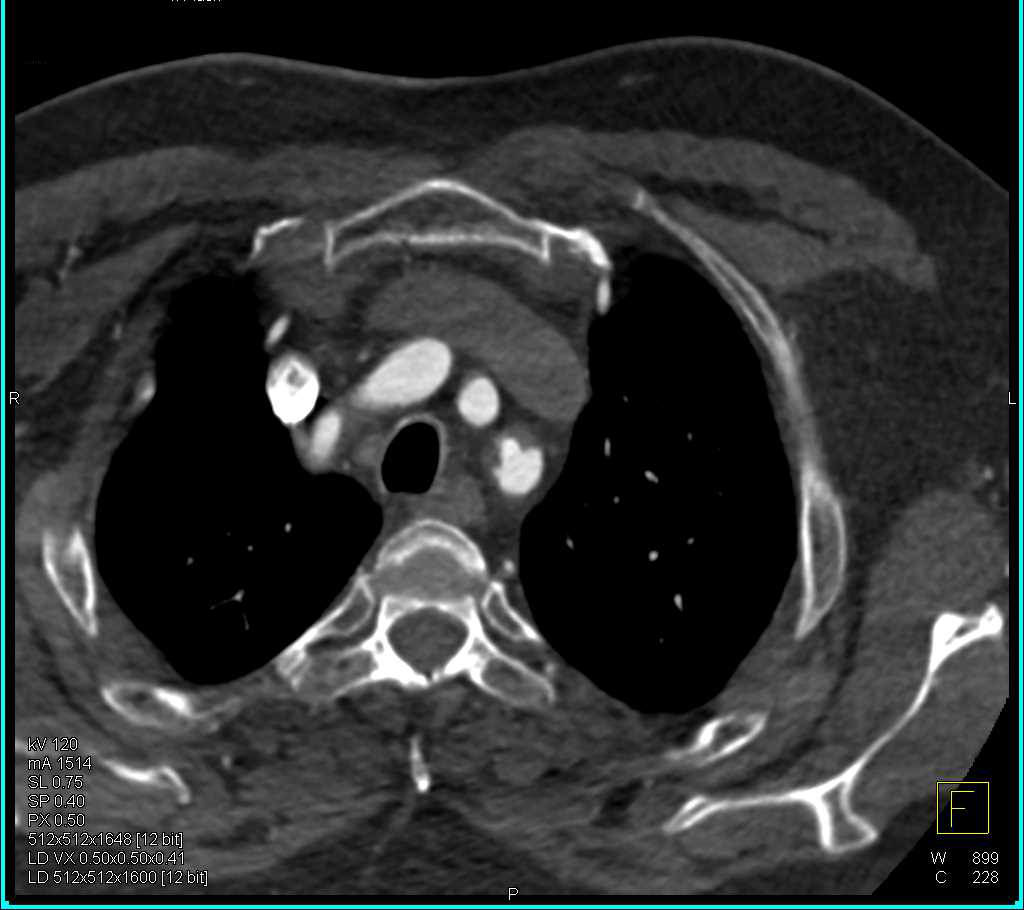

Aortic Valve Stenosis and Dilated Ascending Aorta